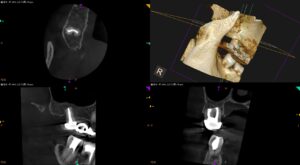

長く持たない治療はやらない!?〜#2 Intentional Replantation 7yr recall

以前の治療の経過観察。 【加筆・追記版】長く持たない治療はやらない!?〜#2 Intentional Replantation 6yr recall Intentional Replantationから7年が経過していた … 続きを読む 長く持たない治療はやらない!?〜#2 Intentional Replantation 7yr recall